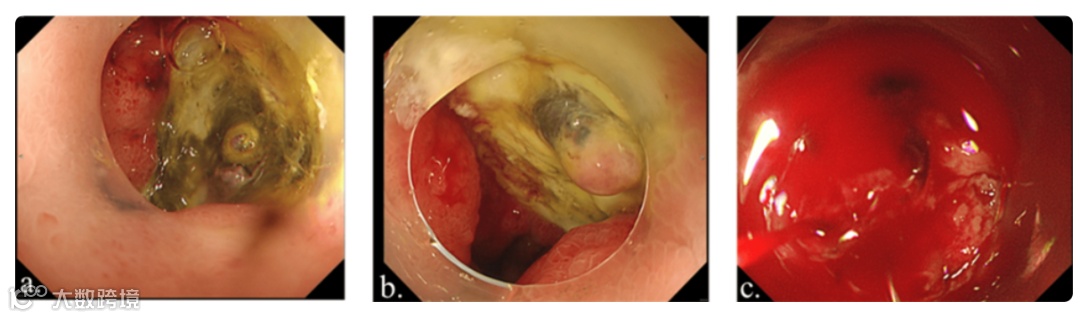

术后第三天,患者出现腹痛和大量黑便。血检显示血红蛋白3.8 g/dL,怀疑为PUD。紧急上消化道内镜检查诊断为十二指肠溃疡(图3a)。由于未发现活动性出血,且考虑到再出血风险,未进行止血干预。患者接受了6单位红细胞输血,并开始使用PPI治疗,同时禁食。凝血酶原时间-国际标准化比值(PT-INR)为1.18,活化部分凝血活酶时间(APTT)为26.2秒,表明患者未处于出血状态。

图3. 上消化道内镜检查结果

术后第五天进行第二次上消化道内镜检查,未见再次出血,溃疡基底部可见白色覆盖物,处于愈合阶段(图3b)。然而,次日凌晨,患者再次发生十二指肠溃疡大量出血,导致休克。紧急上消化道内镜检查显示十二指肠溃疡基底部有活动性喷射状出血(图3c)。尝试进行止血干预,但因出血严重而困难。内镜检查过程中,患者病情逐渐恶化,血压显著下降,最终发生无脉性电活动。尽管进行了心肺复苏和大量输血等抢救措施,患者仍于当日死亡。